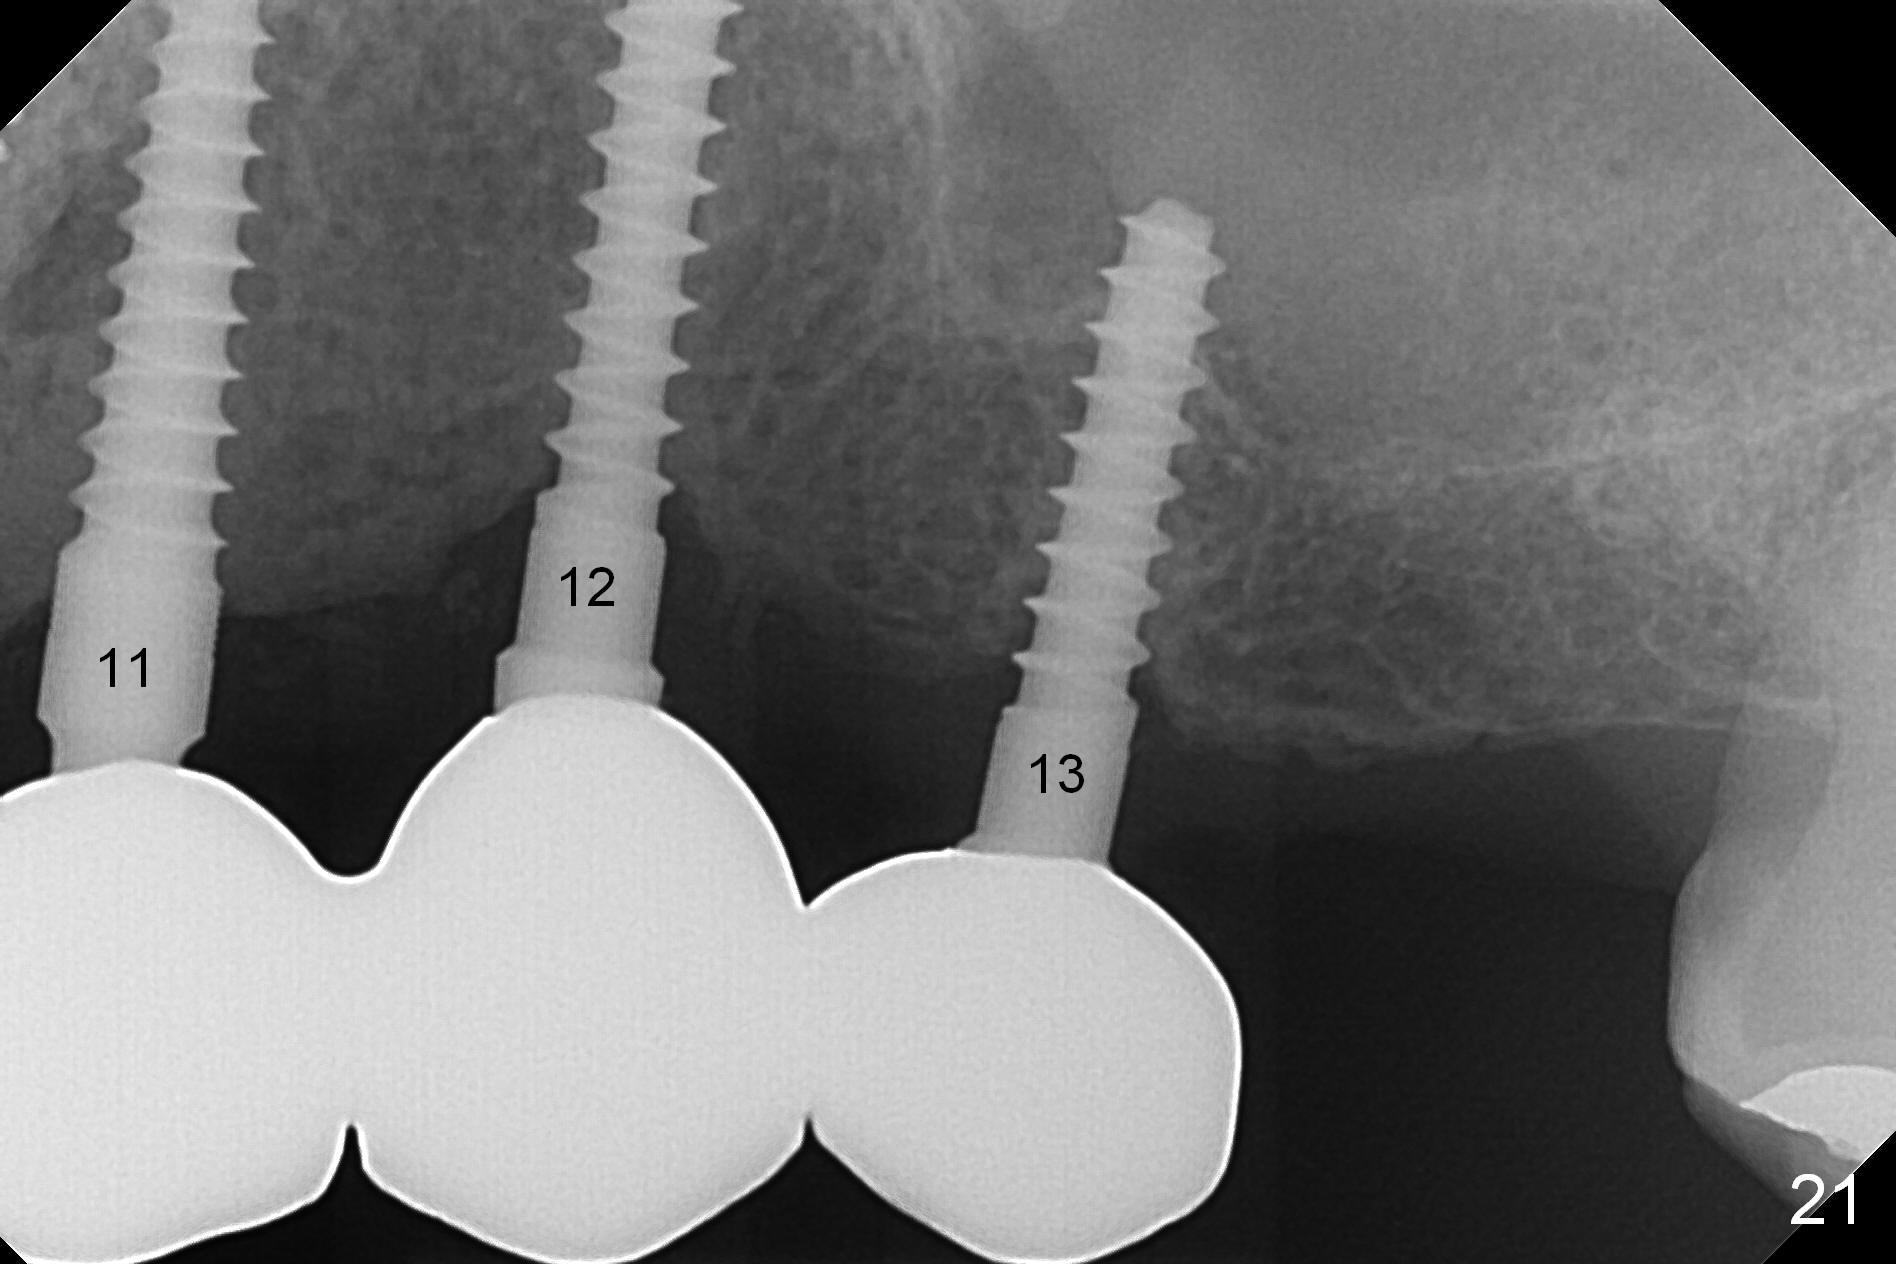

Six months post cementation, the tooth #9 becomes symptomatic. Is it possible that the implant at #10 is too close to the root of #9? It is asymptomatic after pulpotomy, but the tooth fractures equi/supragingivally. Two PAs taken while RCT show osteointegration at #10-12 (Fig.18,19). While the bone density increases at #10 regular implant, there is minimal bone loss around the 1-piece implants 13 months post cementation (18 months postop, Fig.20,21). The gingiva remains healthy 19 months post cementation (Fig.22). 76岁病人突然打电话说一个植牙牙冠松动,其实9号牙(自然牙)折裂,6,10-13号牙植牙好像没有骨质吸收(图二十三至二十五),10-13牙位牙龈健康(图二十六,行使功能五年)。9号牙牙冠重新粘固后,显示前牙深覆合,深覆盖(图二十七,二十八)。如果再次脱落需要植牙,选择一段式有助于植入和修复,因为植体和基台直径小。两段式植牙相对基台直径至少4,或者4.5毫米,前牙修复显得笨重。由于9,10牙根和植体接近,9号牙植体需要偏小而长,3x14或者15毫米(图二十九)。